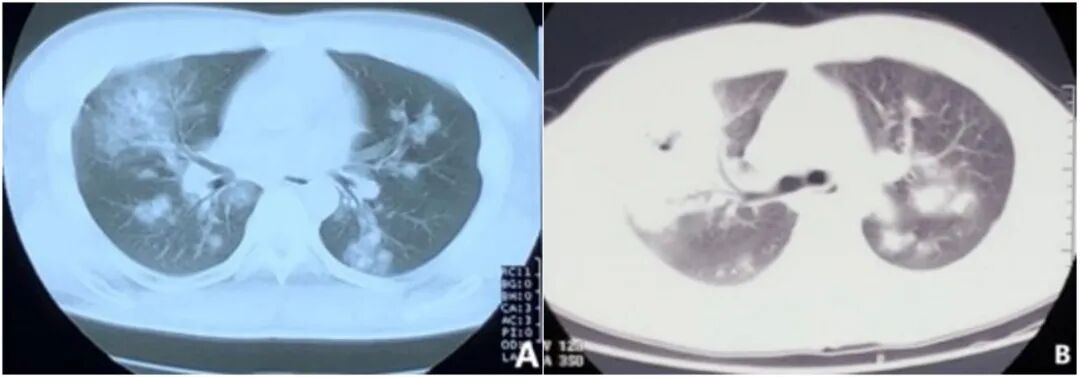

1  患者外院CT

注:3月2日外院CT提示右肺可见大片高密影,左肺可见散在病灶;3月6日外院CT提示双肺多发斑片状影,右侧为甚。

图片

2  我院急诊CT(3月9日)

注:双肺多发病变,感染可能性大,其中右上肺可见空洞。